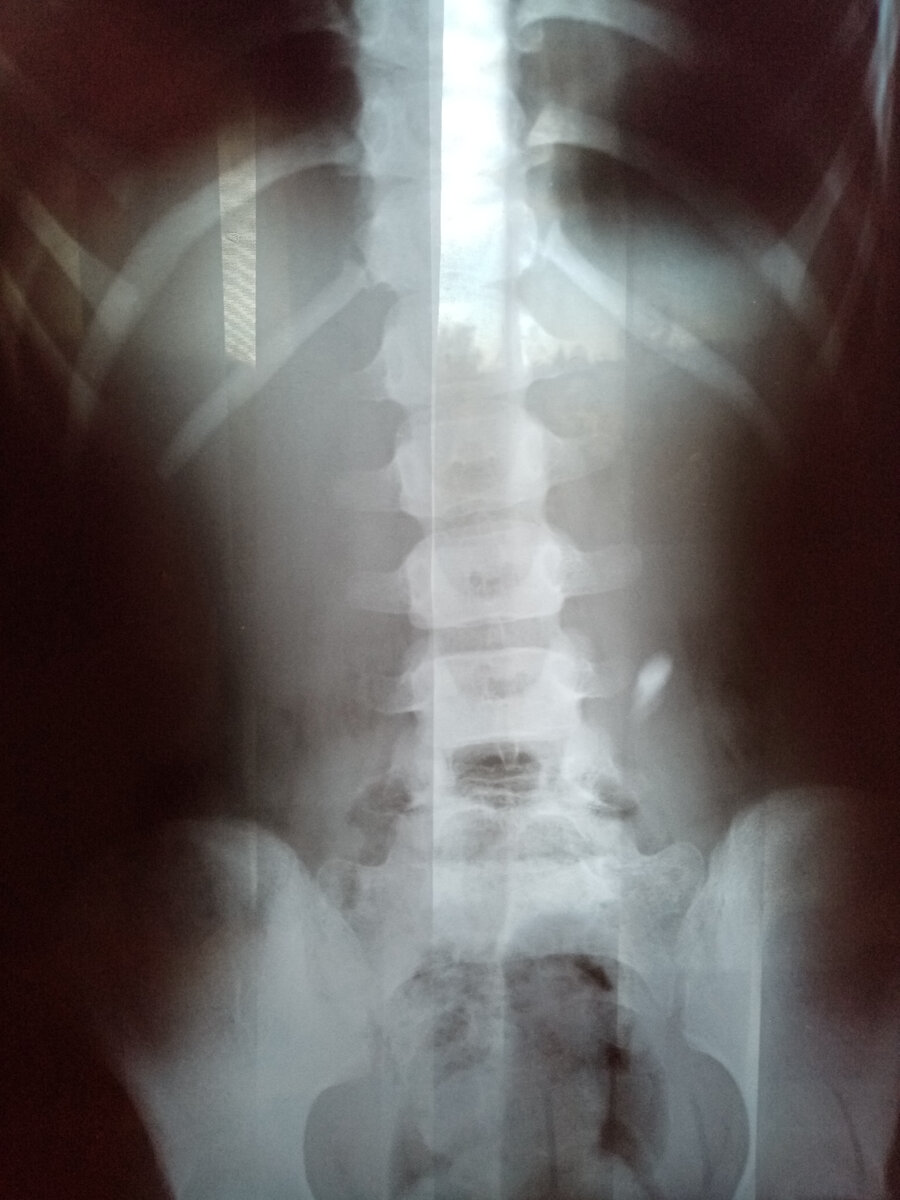

Это случилось ещё летом, но поделиться решилась только сейчас, успокоилось и подзабылось. Конечно, это совсем не по теме моего канала, да и писать я совсем не умею, но во взаимных подписках у меня много мамочек с детьми, возможно наш опыт будет кому-то полезен. В общем, старшая дочь 7 лет ( казалось бы 7 лет, как и главный вопрос - зачем????!!!!! ). А произошло всё случайно. Пока я возилась в кухне, дети сидели на диване, смотрели мультики и параллельно разбирали игрушечный фонарик из "Фикс прайса". Разобрали без труда, а внутри "батарейки - таблетки" , интересно же... И вот, старшая лежит уже на диване и разглядывает одну из них, а младшая прыгает на том же диване, батарейка естественно вываливается из руки и падает прямо в рот и моментально проглатывается. Старшая идёт ко мне и сообщает о случившемся. Сказать, что я испугалась, ничего не сказать... В голове ужасные картины с прожженым горлом или пищеводом, стомы, каллоприемники и т.д и т.п... Позвонила в скорую, сказали, что сейчас приедут, а пока вызывать рвоту. Вызывали, но батарейка уже была далеко. На Скорой нас отвезли в травмпункт, там нас осмотрел хирург, сделали рентген и оказалось, что батарейка уже в пищеводе.

Хирург дал рекомендации: ничего не делать, жить обычной жизнью и тщательно проверять содержимое горшка, а через три дня, если так ничего и не выйдем прийти на повторный снимок. Я подуспокоилась и поехали мы домой. Дома залезла в инет и начиталась, что через два часа батарейка начинает окисляться, отравлять и прожигать пищевод. Теми же ногами, мы поехали со снимком в областную больницу, предварительно поели и попили, что бы процессы в организме проходили быстрее. А зря, а может и не зря... Хирург в областной больнице порекомендовал сделать ФЭГДС, но мы поели, а перед данной процедурой нельзя кушать несколько часов.

Поэтому, нас опять отправили домой и сказали приехать утром на голодный желудок. Ночь я наверное не спала, еле дождавшись утра - поехали. В больнице сделали повторный снимок.

Оказалось, что батарейка почти на выходе, нужно только сходить в туалет, а с этим у нас проблемы, запорами мучаемся. Но врач разрешил сделать клизму, наш хирург говорил, что клизма не нужна. Приехали мы домой и приступили к неприятной процедуре. И наконец-то она вышла чистенькая и невредимая, такая же блестящая и без следов окисления, вот это было облегчение. Возможно, нам попалась качественная батарейка и поэтому она не окислилась, а может на это нужно больше времени.